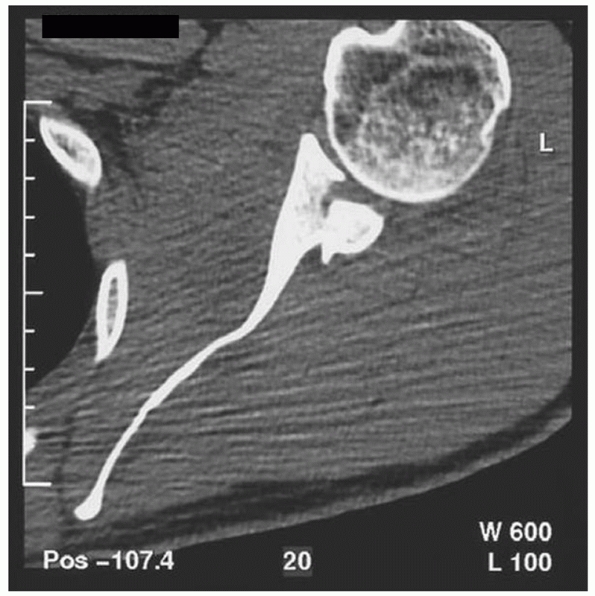

It is, however, useful to assess the size, location, and degree of

displacement of fragments in coracoid, acromion, and glenoid fractures.

In glenoid fractures, it is also helpful to evaluate the position of

the humeral head in relation to the glenoid fossa or fracture fragment (Fig. 37-2).